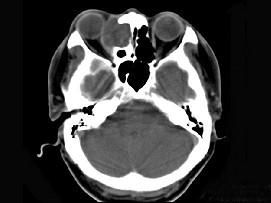

问题 女性38岁,右侧眼球运动障碍伴眼球突出4个多月,CT扫描如图,请选择正确的描述和答案 ( )

选项 A、考虑为右侧筛窦黏液囊肿 B、考虑为筛窦癌 C、囊性肿块向右侧眼眶内突入,压迫内直肌 D、右侧眶内壁呈受压变薄、断裂 E、右侧筛窦内可见囊性肿块影,边缘光整

答案 ACDE